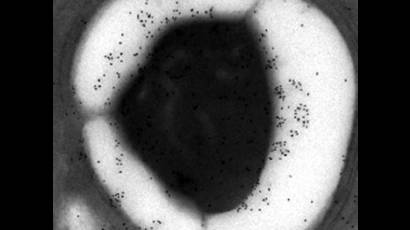

El almidón modificado podría curar el paludismo

El almidón, una cadena de azúcares, es la principal reserva de energía en el maíz y la papa.